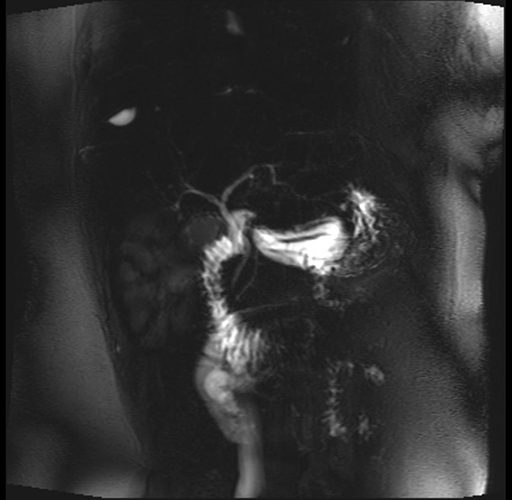

Imaging Analysis

Look through the patient's CT scan to identify any areas of concern for the necessary procedure.

Based on your CT findings, which issue(s) are present and would give reason for "planned slowing down moment(s)" in this case?

Considering a standard distal pancreatectomy procedure, what step(s) of the operation would you do differently in this case?